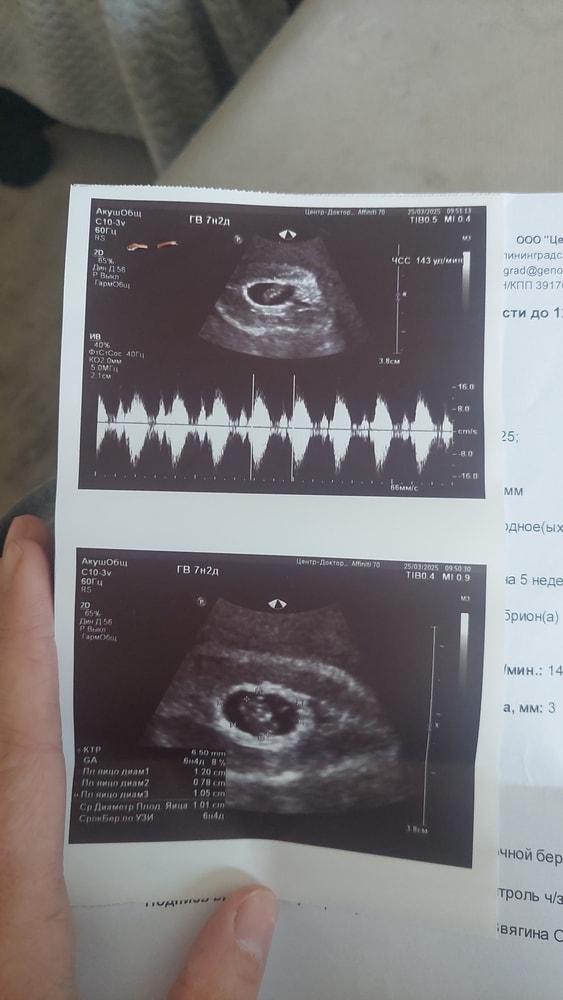

В пятницу 28 числа выписали с отслойкой и чуть почуть мазало с понедельника по узи все было хорошо ктр 7.4 мм сердцебиение + пя 12 мм , отслойка 10×8мм

Как врач сказала что все нормально , и т.д.